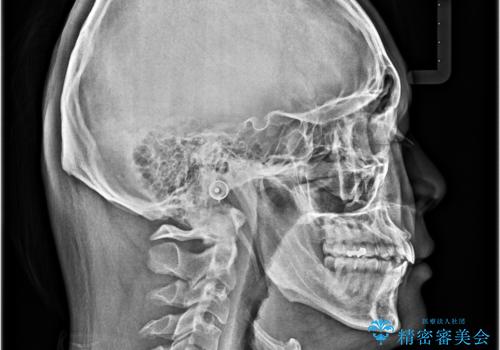

右上第一小臼歯は歯根癒着により移動せず、左上第二小臼歯は移動はするものの非常に動きが鈍かったため、抜歯したスペースを閉じるまでに非常に時間がかかってしまいました。

患者様には辛抱強く治療にお付き合いいただき、すっきりとした口元に仕上げることができました。